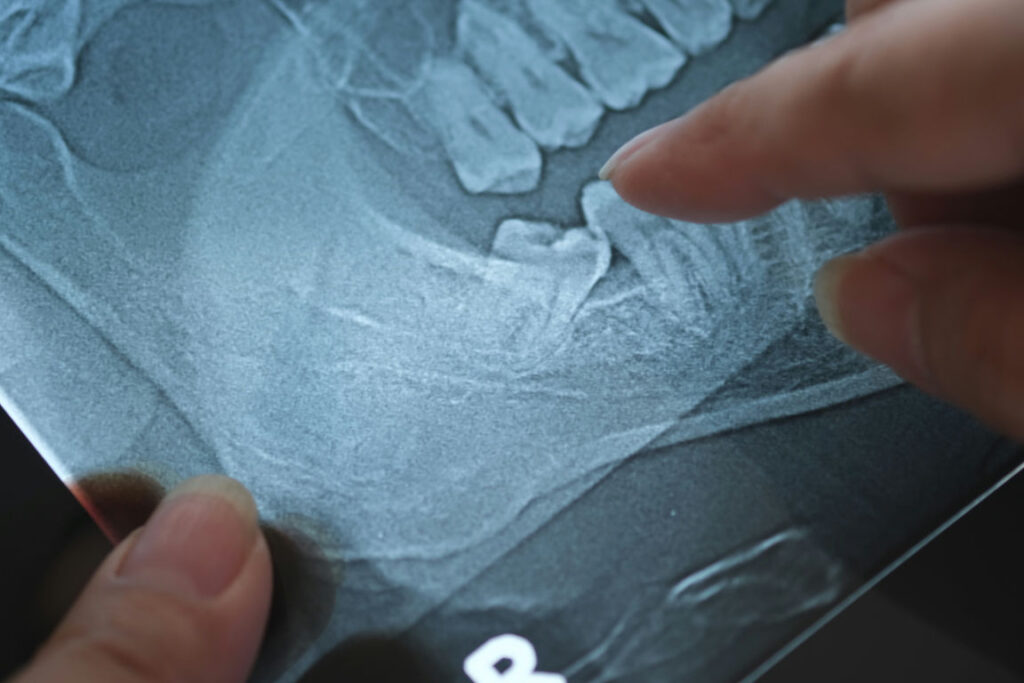

When a wisdom tooth doesn’t have enough room to emerge, it becomes “impacted.” This means it remains stuck in the jawbone or grows in sideways, pressing against the roots of neighboring teeth. This isn’t just a minor discomfort; it can lead to cysts, gum disease, and even damage to the jawbone itself. In the modern world, this is one of the most common reasons for outpatient surgery. Because our mouths have evolved to be smaller, these “trapped” teeth have become a significant health hurdle that our ancestors rarely had to deal with during their shorter lifespans.

Dentists generally monitor these teeth with X-rays starting in the early teens to catch potential problems before they start. If a tooth looks like it’s going to cause a “pile-up” in the dental row, extraction is usually the safest bet. This medical necessity highlights the gap between our ancient biology and our current needs. We are essentially living in a high-tech world with “hardware” that was designed for a much rougher environment. Dealing with impacted wisdom teeth is simply part of the price we pay for having the refined, smaller faces that characterize the modern human look today.